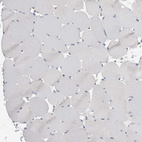

Immunohistochemistry analysis in human kidney and skeletal muscle tissues using HPA026077 antibody. Corresponding GATM RNA-seq data are presented for the same tissues.